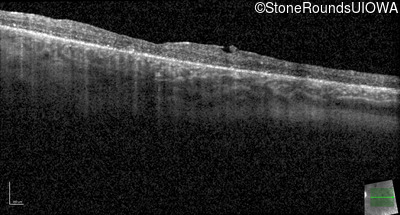

Optical Coherence Tomography - Right - 20/50

Exemplar / OCT Stack